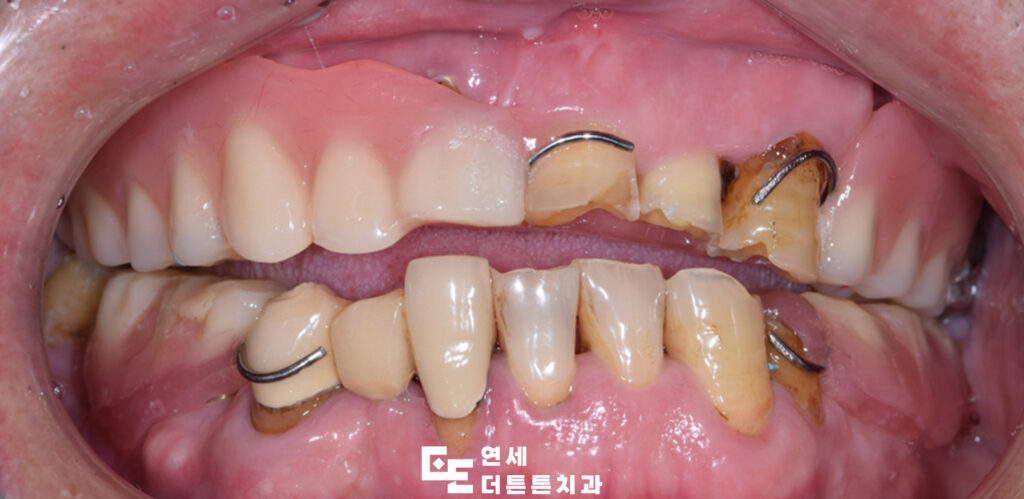

환자분께서는 구강 내 어금니 부위를 거의 상실하신 채로, 남아 있는 치아들도 부러져 제 기능을 하지 못해 치료 상담을 위해 방학역치과에 내원해 주셨습니다.

다수의 치아가 손상되거나 상실된 상태로 내원하였으며, 잔존 치아 또한 심한 우식과 변색, 구조적 약화가 동반된 상태였으므로 일부 치아는 보존이 어려운 상태였기 때문에 발치를 진행하였고, 남아 있는 치아 중 사용 가능한 치아는 신경치료 및 보강을 통해 최대한 활용하는 방향으로 치료를 계획하였습니다.

먼저 예후가 좋지 않은 치아들을 발치하고 결손 부위에는 임플란트를 식립하여 기능적인 지지 기반을 형성하였으며 최종 보철물이 들어가기 전 기간동안 사용하실 수 있는 임시틀니를 제작해 드렸습니다. 임플란트가 뼈에 제대로 붙기까지는 시간이 필요하며, 일반적으로 상악은 약 6개월, 하악은 약 4개월이 소요되어 그 기간동안 사용하시며, 최종 보철물에 대한 전반적인 상담도 충분히 진행할 수 있도록 하였습니다.

이후 기존 치아와의 조화를 고려하여 보철 치료를 진행하였습니다. 치료 과정에서는 단순히 치아를 대체하는 것에 그치지 않고, 교합의 균형과 저작 기능 회복, 그리고 자연스러운 외관까지 함께 고려하였습니다. 특히 전치부의 경우 심미적인 요소가 중요한 부위이기 때문에 치아의 형태와 색상, 배열을 세밀하게 조정하여 전체적인 인상이 자연스럽게 개선될 수 있도록 하였습니다.